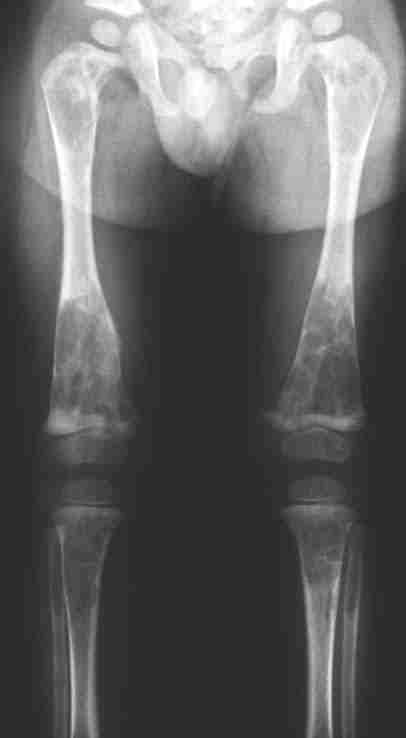

Figure 1: X-ray of lower limbs with lesions typical of fibrous dysplasia